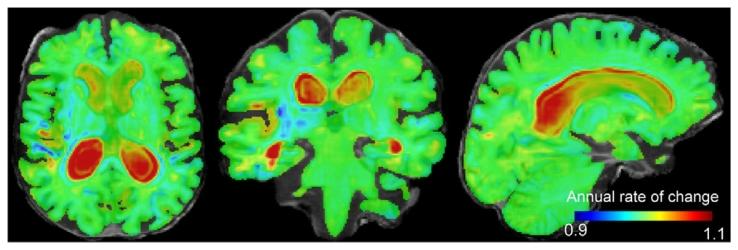

Fig. 5. Jacobian determinant of the 1-year subject-specific estimated trajectory of anAlzheimer’s disease patient overlaid on its non-linear template. Hot colours (> 1)indicate expansion and cold colours (< 1) indicate contraction over time. The valueof each voxel indicates the annual rate of change.

图5 阿尔茨海默病患者1年受试者特异性估计轨迹的雅可比行列式,叠加于其非线性模板之上。暖色(>1)表示随时间扩张,冷色(<1)表示随时间收缩。每个体素的值代表年度变化率。